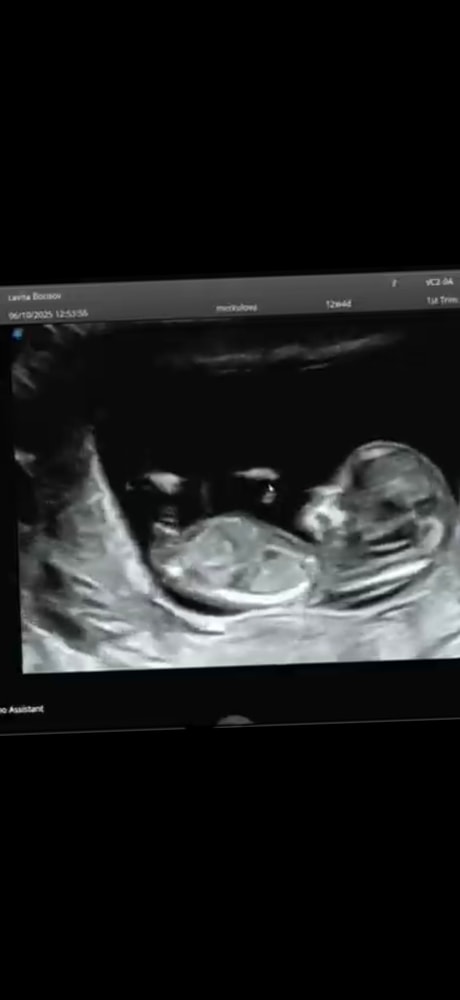

Подскажите на кого похоже ? Мальчик или девочка ?

Пол малышаСрок 12 недель . Скрины с видео , при разном ракурсе половой бугорок меняется